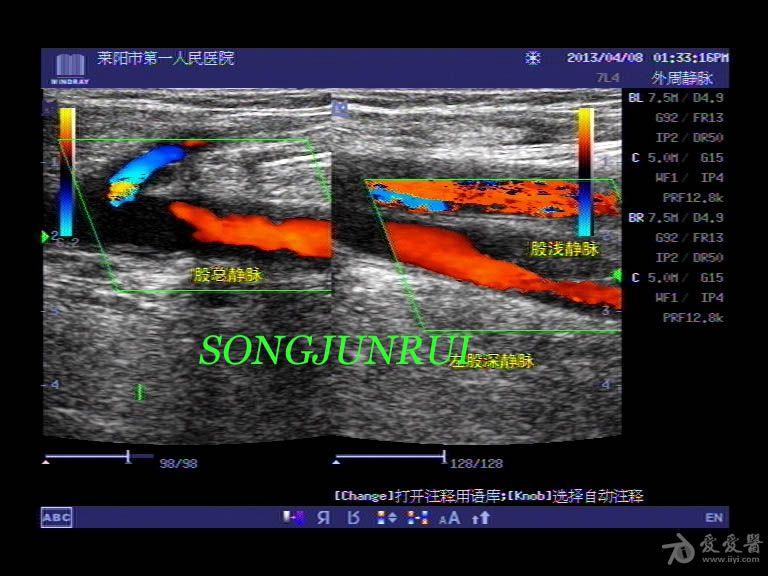

下肢血管解剖图彩超

下肢血管的超声检查及正常声像图